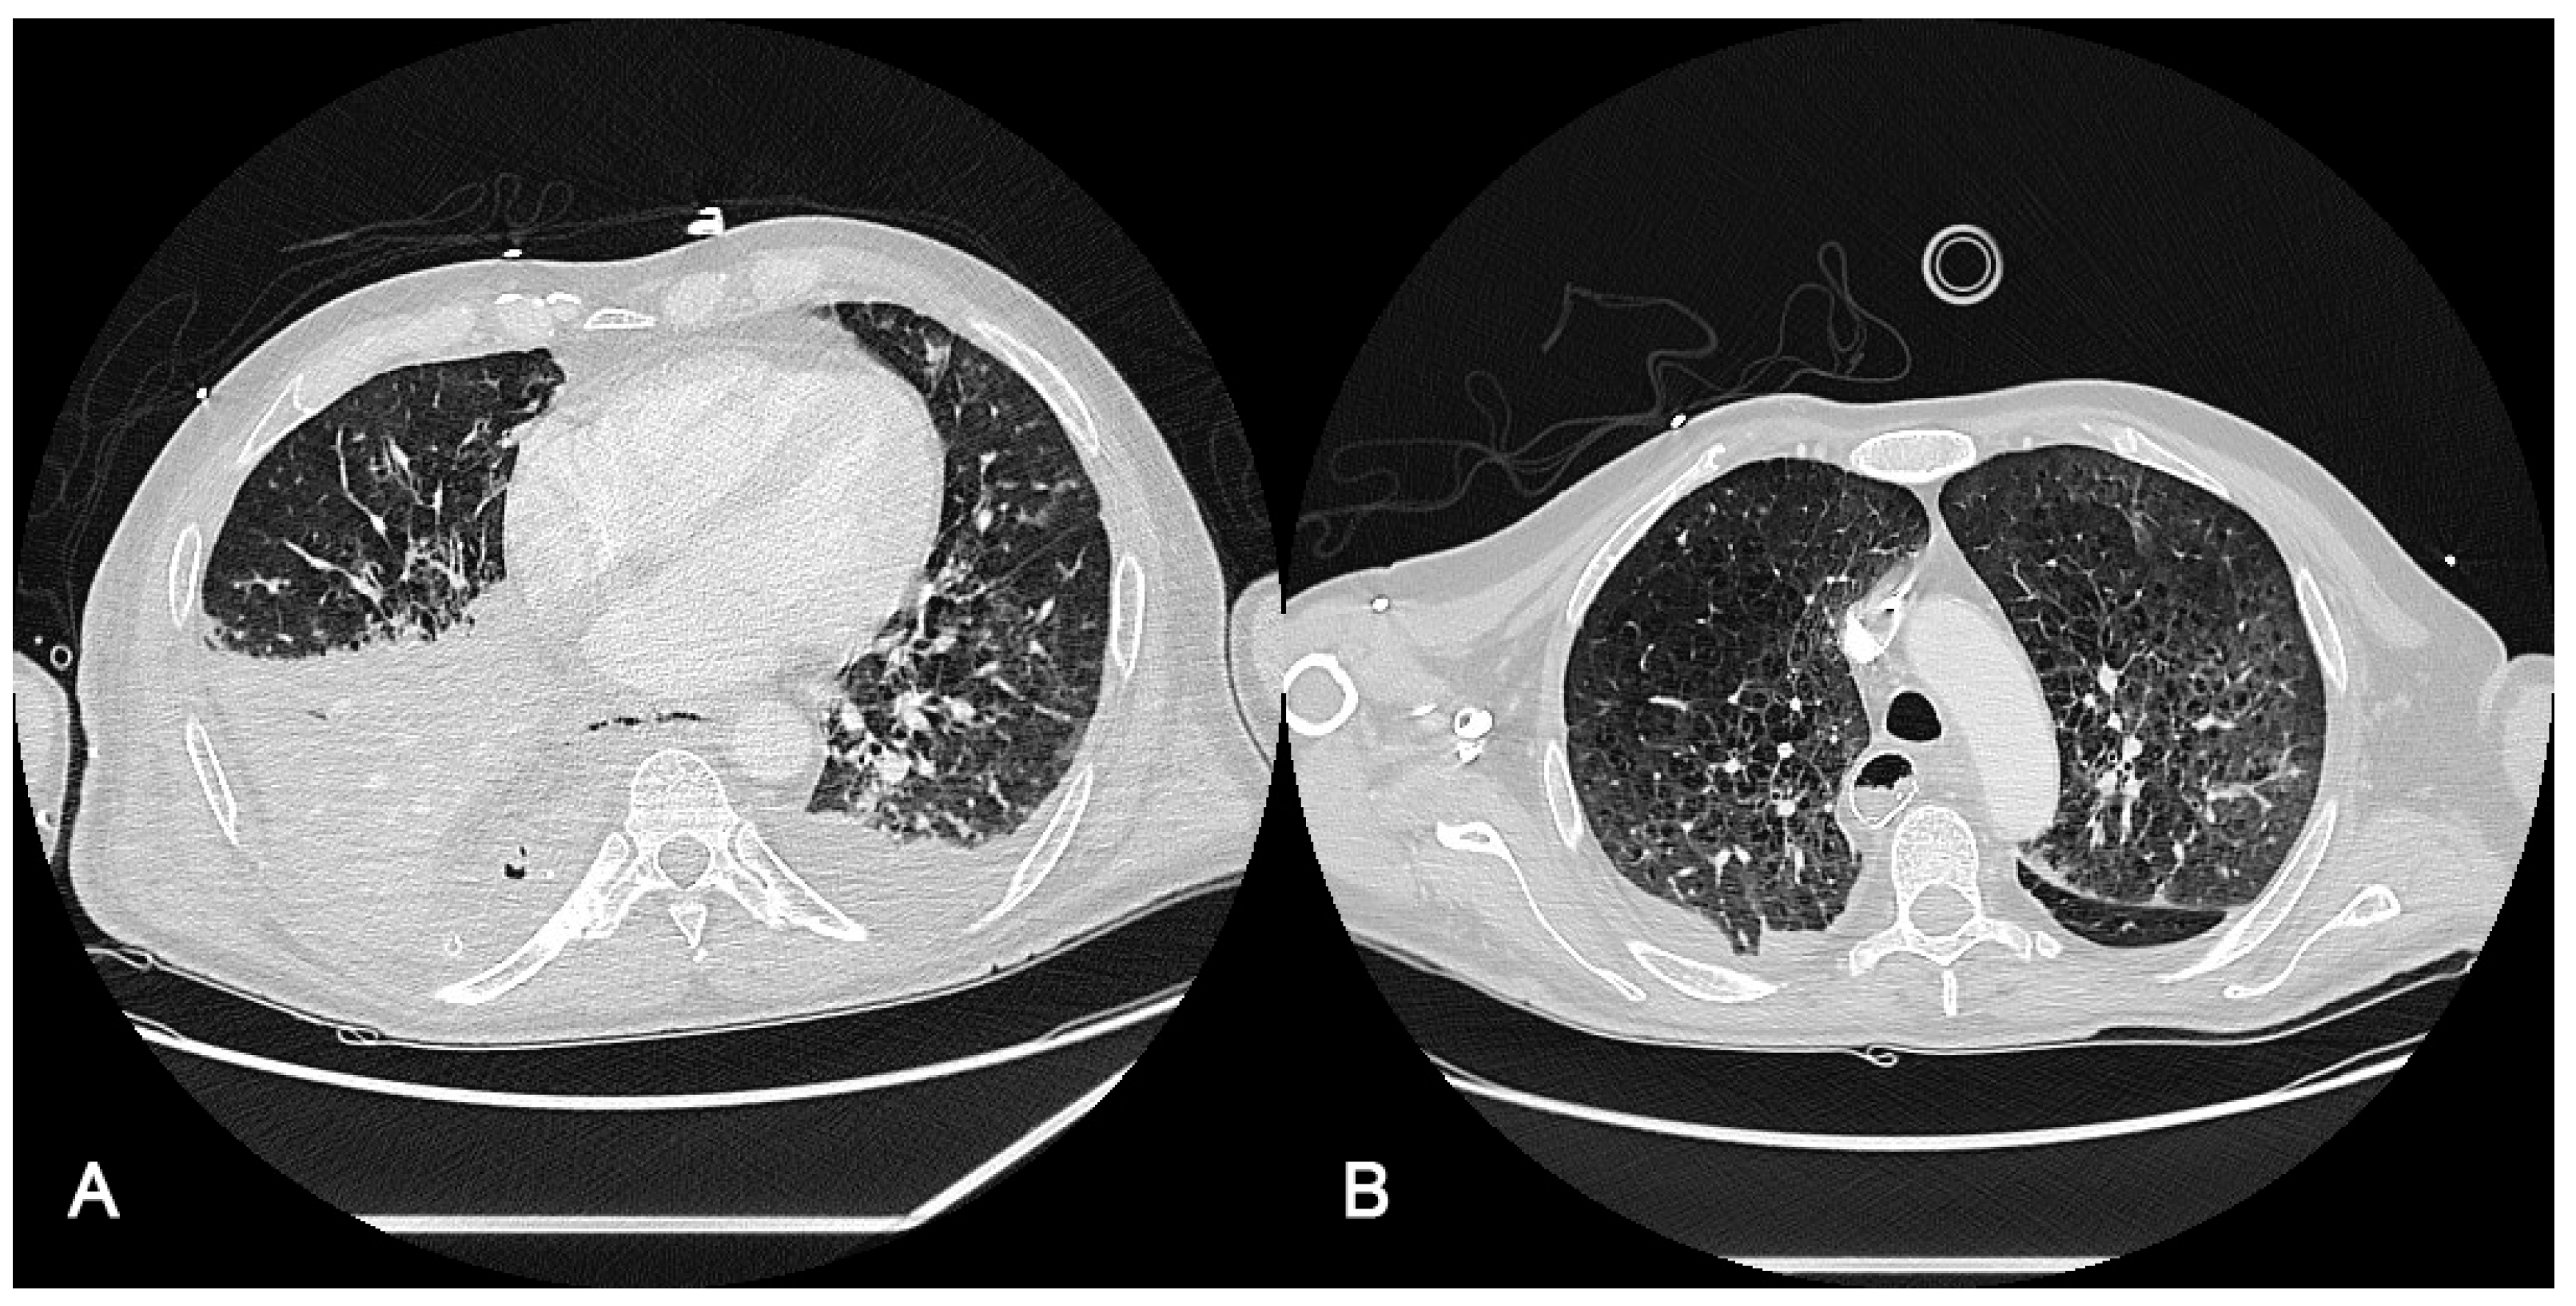

3.3. Radiological Findings